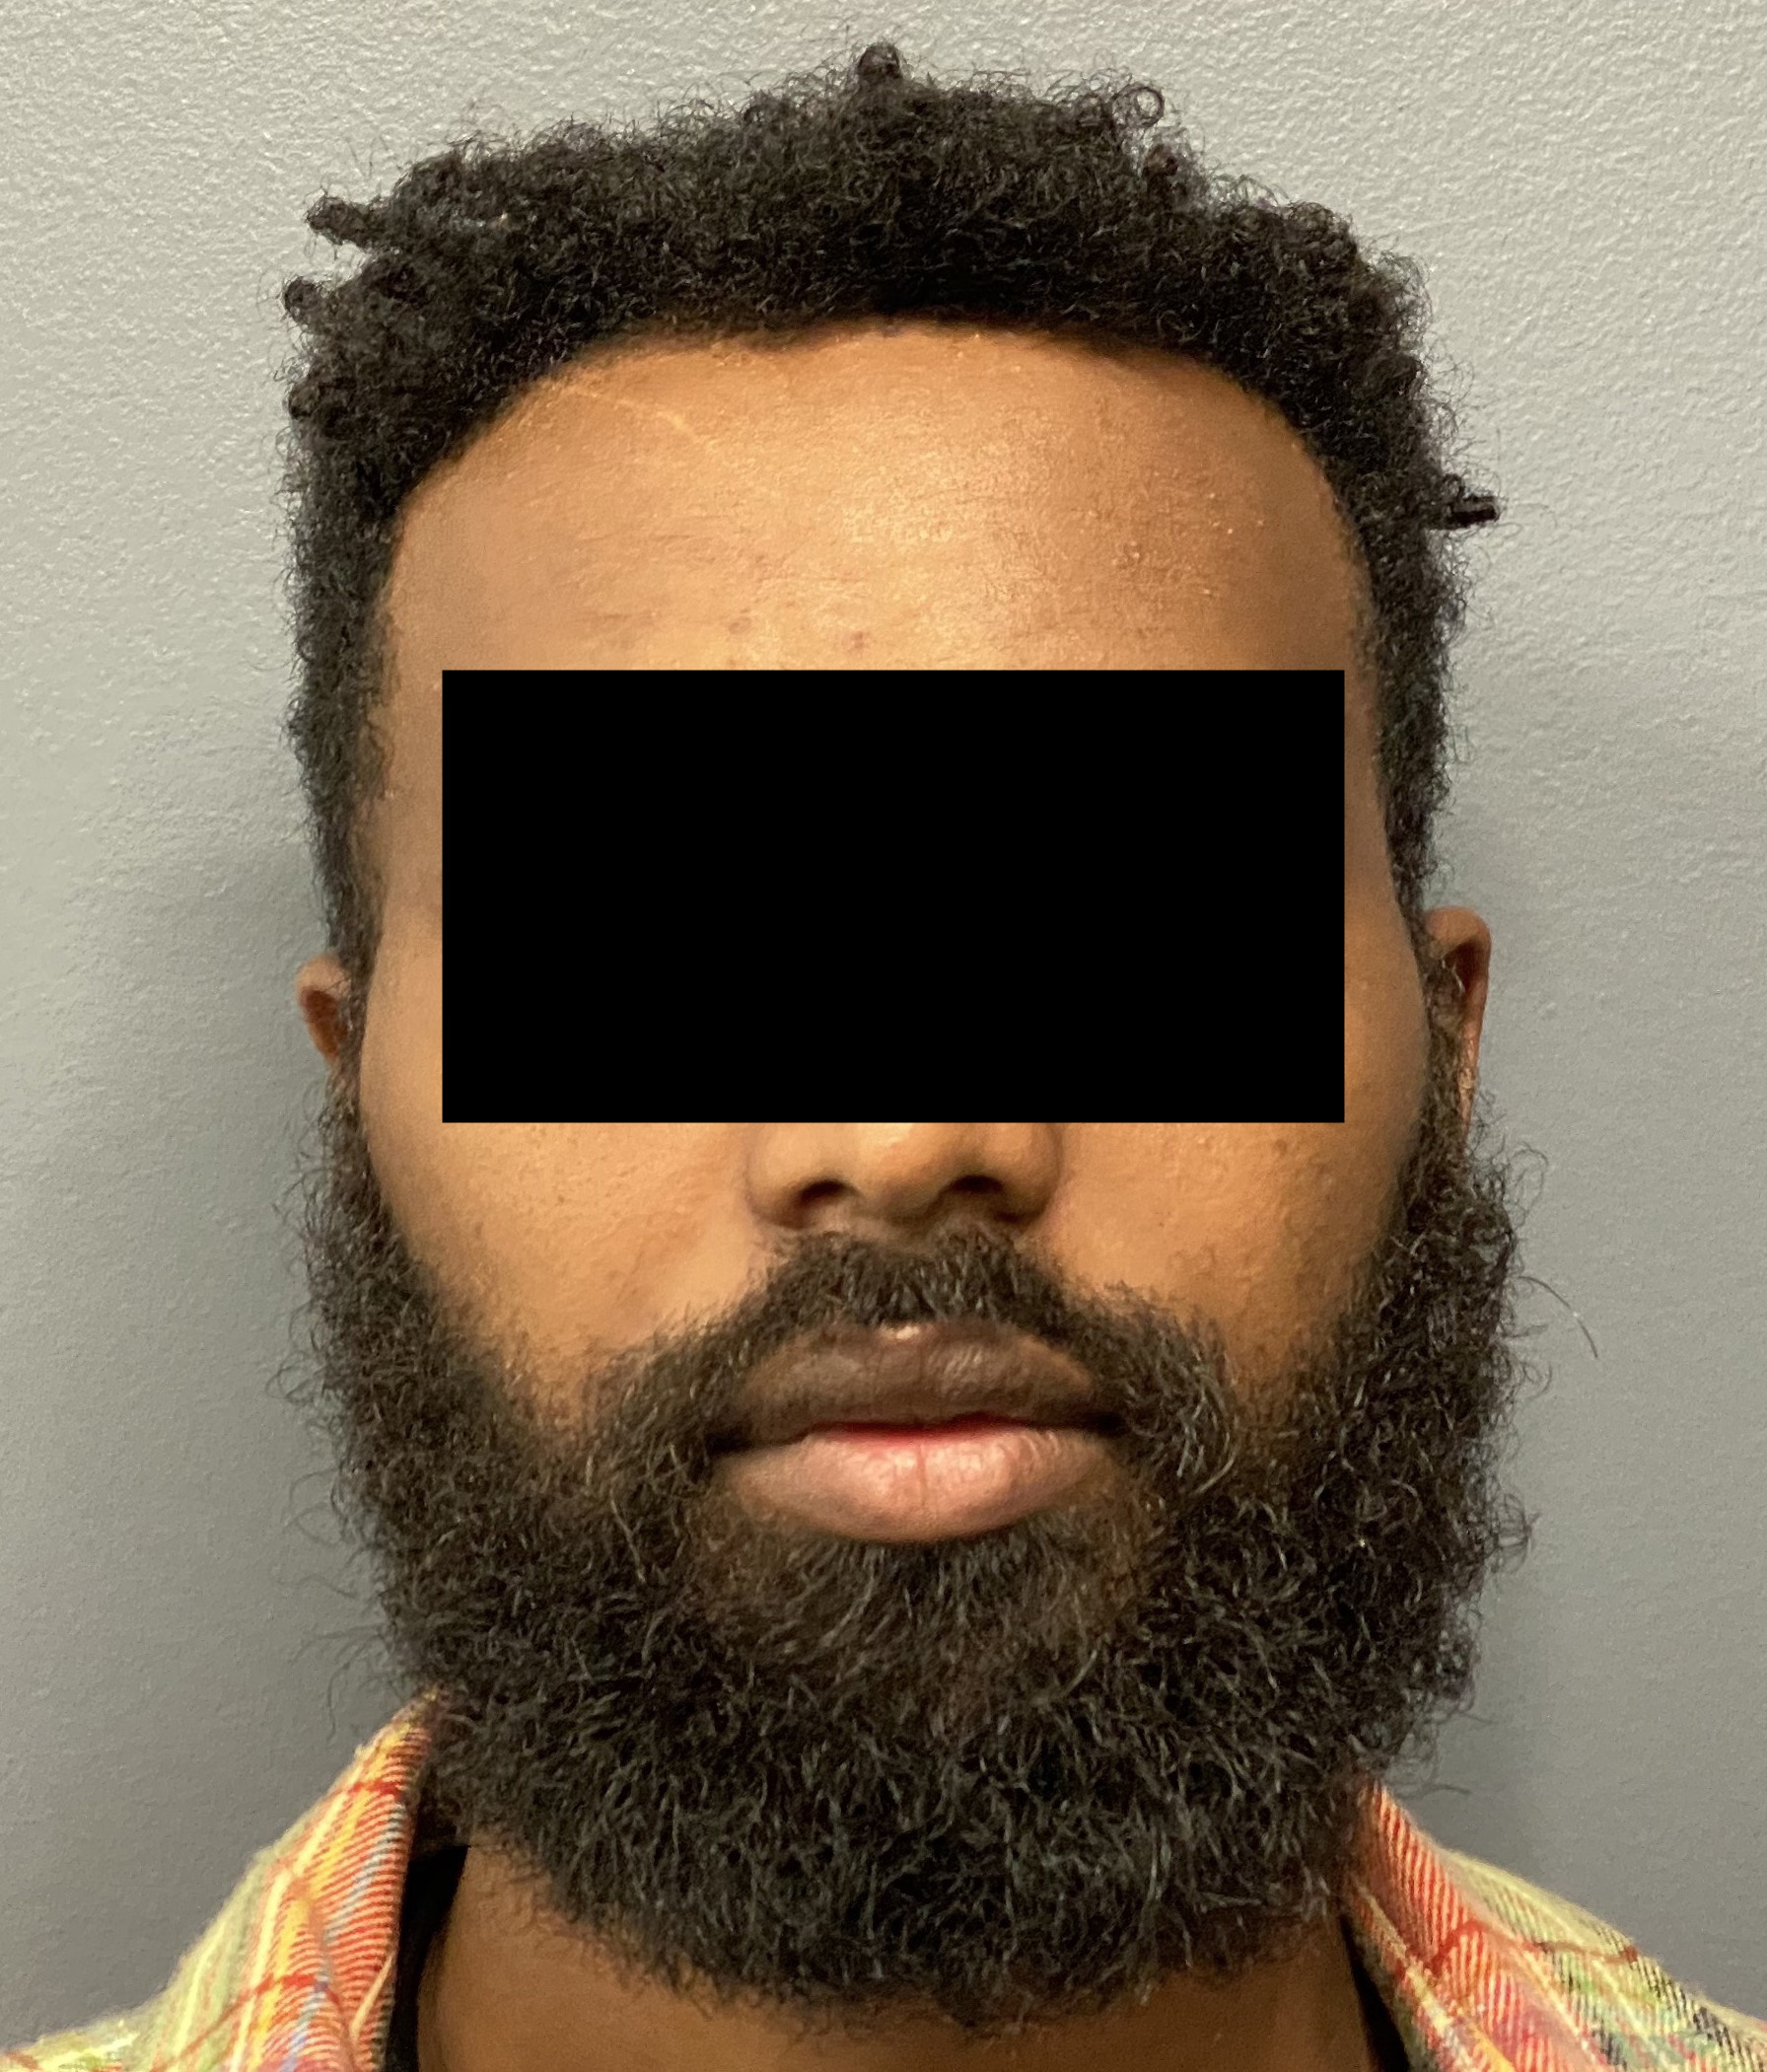

Patient 100

Desire for reshaping of an asymmetric flat back of the head in a shaved head male.

A combined back of the head reshaping procedure was done with a custom skull implant, sagittal ridge reduction and a right temporal muscle reduction.

Desire for reshaping of an asymmetric flat back of the head in a shaved head male.

A combined back of the head reshaping procedure was done with a custom skull implant, sagittal ridge reduction and a right temporal muscle reduction.